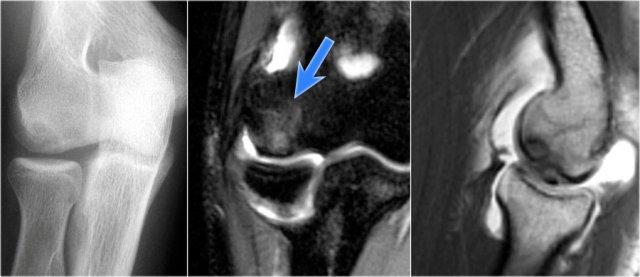

Hình chụp X-quang của một vận động viên bóng chày 15 tuổi với tiền sử đau khuỷu tay 4 năm và gần đây có triệu chứng kẹt khớp.

Có một vùng thấu quang khu trú ở chỏm con và một số mảnh vỡ.

Đây là hình ảnh điển hình của tổn thương sụn xương chỏm con và hiện tượng kẹt khớp có thể là kết quả của các dị vật trong khớp.

Continue with the MR…

MR-arthrogram xác nhận tổn thương sụn xương.

Có gadolinium nằm giữa xương cánh tay và tổn thương sụn xương, cho thấy tổn thương này không ổn định.

Nếu không có gadolinium, hãy tìm dịch khớp chui xuống dưới mảnh sụn xương.

Có một mảnh thể tự do trong ngách sau của khớp quay-cánh tay.

Notice also the fragmentation as seen on the axial image.